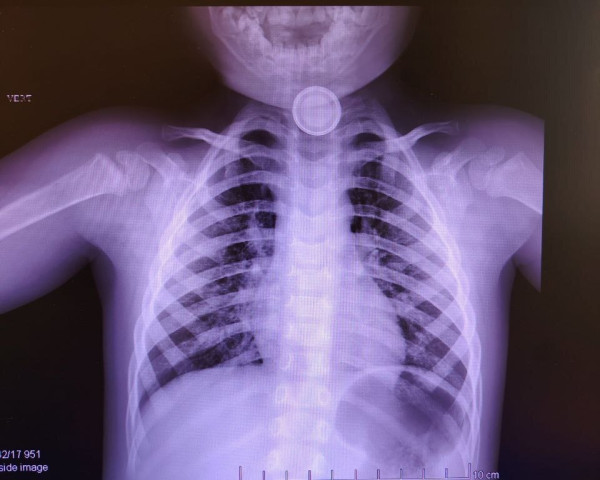

Ребенок попал в больницу с затрудненным глотанием и слюнотечением. В ходе обследования на рентгеновском снимке медики обнаружили, что малыш съел батарейку. Она застряла в пищеводе.

Врачи достали посторонний предмет, однако он уже успел повредил стенку пищевода – юному пациенту диагностировали ожог.

ФОТО пресс-службы Нижневартовской окружной детской больницы